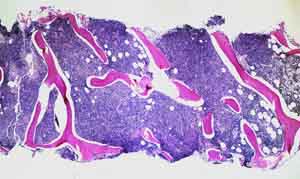

Diffuse pattern.